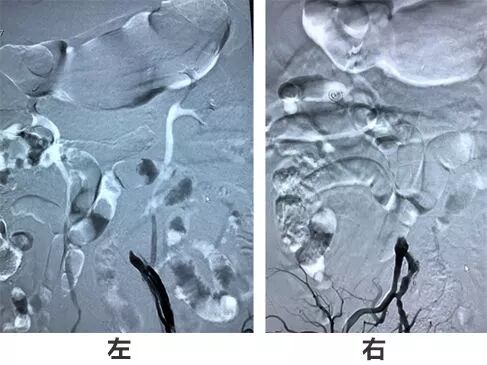

欲从股动脉入路,股动脉置鞘造影示双侧未显影。

桡动脉评估:Allen试验证实无尺动脉代偿,遂行肱动脉穿刺后进入(6F心内科短鞘,6F导引导管)。腹主动脉造影证实双侧髂动脉闭塞,主动脉弓造影示情况良好。

R-CCA情况良好,L-CCA起始端闭塞。

R-CCA

L-CCA